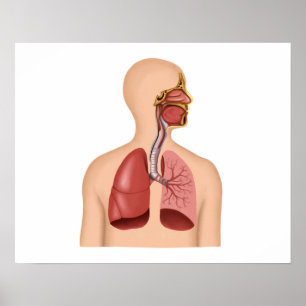

Impressão de Vintage 1908

Preço46,25 €

Impressão 1908 interno do vintage da anatomia do

Preço46,25 €